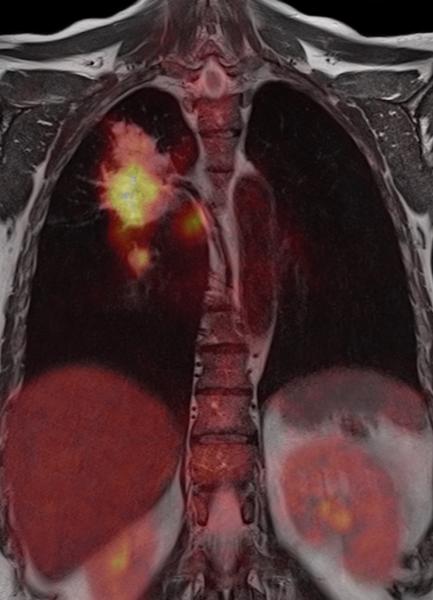

PET/MR: better together or apart? Image courtesy of Siemens, provided by University of Geneva

A good case can be made for the purchase of a hybrid. It merges data from simultaneously performed MR and PET scans, yet has the potential to conduct MR separately. Vendors leveraged the two faces of PET/CT in the early days, when demand for hybrid scans was only beginning. PET/MR can deliver about the same diagnostic information as its CT counterpart. Some believe it can do even more.

Schlemmer admitted as much in his cautionary tale at the ECR. MR provides superior anatomical resolution to CT, he noted, with PET providing metabolic and membrane receptor information. “Together (PET/MR) increases your sensitivity and specificity for tumor detection and characterization,” he said.